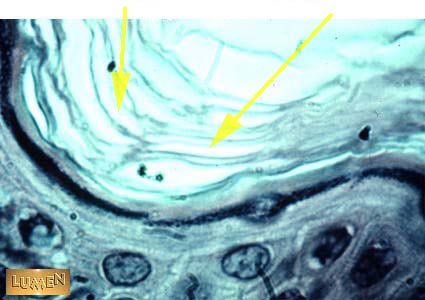

What is this layer called?

stratum corneum